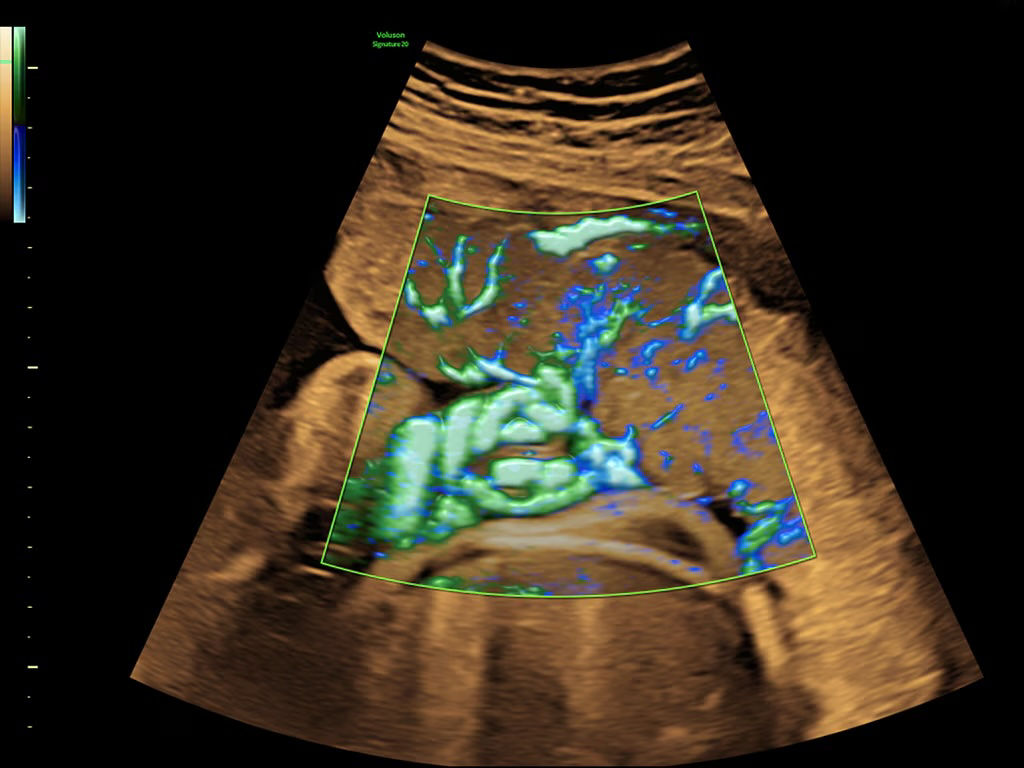

Next level color Doppler that delivers exceptional sensitivity for easy, fast visualization of blood flow, displaying a 3D like appearance as seen in this 27-week fetal heart.